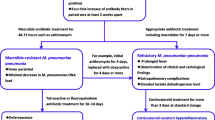

Together with growing use of ML in Japan, resistant strains increased rapidly year by year (Fig. 2) [36]. Along with greater overall prevalence of M. pneumoniae infection in 2006, MLr strains increasingly were isolated and identified in diverse regions across Japan.

The clinical course of patients with MLr M. pneumoniae infection appears to be prolonged [36, 66, 71, 72]. Patients infected with MLr strains mostly had been treated with ML previously [36, 40]. Among CAP patients infected with MLr, treatment frequently was changed from ML to MINO or levofloxacin (LVFX) because of either persistent symptoms (i.e., fever and cough) or unresolved or worsening chest radiographic abnormalities. In our observations, treatment was changed from ML to MINO or LVFX in 8.2% of patients with MLs strains and in 39.7% of patients with MLr strains, representing a significant difference between the two patient groups (P < 0.01). ML also was more frequently discontinued in favor of MINO among MLr patients than MLs patients in a report by Suzuki et al. [71]. Neither LVFX nor MINO are recommended for pediatric patients. However, when ML are ineffective against M. pneumoniae infection, pediatricians have little choice of antimicrobials except for MINO. In adult inpatients infected with MLr strains, antibiotic agents were changed from CAM to intravenous pazufloxacin when symptoms did not improve [66]. Orally administered respiratory FQ such as moxifloxacin, sitafloxacin, and garenoxacin may be selected for adult outpatients with MLr strains.

Among clinical features of MLr M. pneumoniae infection, fever duration has been significantly longer than for MLs-strain infection. In our data, fever persisted after ML initiation for 1.6 ± 0.8 days in MLs M. pneumoniae infection and for 4.1 ± 2.3 days in MLr-strain infection, showing a significant difference (P < 0.01). In other studies, febrile days during ML administration also were significantly greater in MLr-infected patients than in MLs-infected patients (3.5–4.0 days vs. 1.0–1.5 days) [71, 72]. Furthermore, the mean duration of persistent cough after ML administration was 7.0 days in MLs-infected patients and 11.4 days in MLr-infected patients [72]. Finally, the efficacy rate of ML therapy was 91.5% and 22.7% in MLs- and MLr-strain infections, respectively [72].

In the future, alternative treatment strategies, such as promptly initiated steroid therapy, might be considered for patients with MLr strains as a symptomatic measure [95–97].